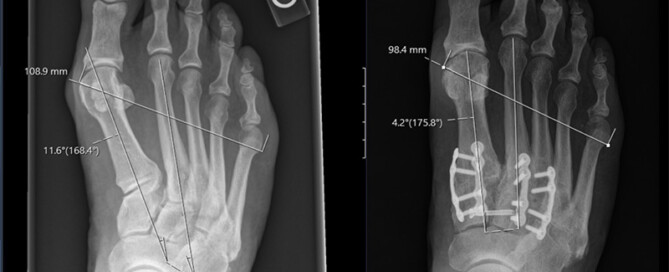

Hey, Let's Talk Bunions... Again So, you had bunion surgery and thought you were done with the whole ordeal, but your bunion decided to make a comeback. Well, don't lose hope. I'm here to talk about an exciting and effective method called Lapiplasty. This could be the solution you've been looking for! First Off, What [...]